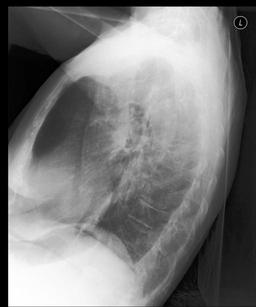

We found that many lateral acquisitions in the dataset were unexpectedly labelled as frontal (Figure 7(a)). Some images contained only noise (Figure 7(b)), non-human samples (Figures 7(d) and 7(e)) or incorrect anatomy (Figure 7(g)). Often, acquisitions with an incomplete field of view (FOV) (i.e., the lungs are not completely visible) were repeated (Figure 7(c)). Lastly, post-processed images were detected by the algorithm such as contrast-enhanced scans (Figure 7(i)) that are not often used for diagnostic purposes in clinical practice.

Curation of imaging datasets

CXR datasets [36] often contain multiple image acquisitions in a single visit due to data quality issues such as a limited field-of-view or scanning the wrong body part (Figure A.7). Unlike [9, 32, 81], we conduct curation to choose higher quality images among the potential candidates instead of performing a random selection. For this step, a separate BioViL-T is trained on ‘clean’ studies with single acquisitions and later used in a zero-shot setting to detect out-of-distribution samples [26, 27] arising from the re-imaging process. The candidate is selected as follows: for a margin . This approach is applied to enhance the quality of the temporal classification dataset given its limited size.